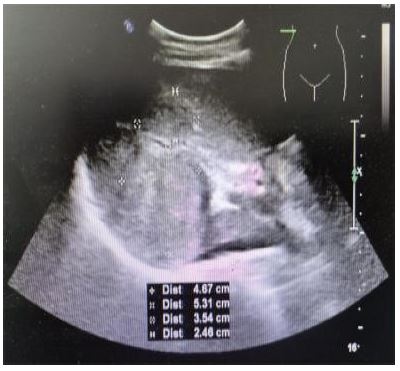

A 56-year-old male patient was admitted to the hospital due to persistent fatigue and shortness of breath lasting for more than 2 months. An ultrasound (Figure 1) performed at an external facility revealed a hepatic shadow that has not improved despite treatment. On April 12, 2017, the patient underwent pancreaticoduodenectomy followed by intraperitoneal chemical particle implantation for the treatment of a pancreatic cyst associated with chronic pancreatitis. Laboratory tests revealed elevated levels of C-reactive protein and abnormal liver function. AFP (-), CEA (-). MRI of the abdomen (Figure 2A-G) showed a large mass measuring approximately 81×61 mm in the right posterior lobe of the liver, characterized by a “double-ring” appearance at the edge. The mass exhibited low signal intensity on T1WI, slightly high signal on T2WI, mild diffusion restriction on DWI, inhomogeneous enhancement on the arterial phase, decreased enhancement in both the venous and delayed phases, and low uptake on the hepatobiliary phase. Localized intrahepatic bile duct invasion within the right lobe of the liver, accompanied by distal dilatation, edema, and abnormal perfusion of the surrounding liver tissue. MRI findings suggest a possible infectious liver lesion, and the tumor could not be drained. Pathological sections of the biopsy obtained from the local hospital consultation (Figure 3) showed fibrous tissue hyperplasia, foam-like histiocyte aggregates observed under the microscope, small spherical fungi with a powder-stained appearance in the cytoplasm, significant neutrophilic infiltration in the interstitium, and filamentous mycobacterial clusters visible at the tissue edge. Rabbit immunohistochemistry of tissue block B showed positive staining for CK (Pan) in residual hepatocytes and for CD68 in histiocytes. Special stains performed on tissue block B revealed reticular scaffold breaks on Masson staining, reticular fibers, positive staining with PAS, and silver stains. The pathological diagnosis of the liver tissue demonstrated morphology consistent with Actinomyces infection, with special staining suggesting a concomitant Cryptococcal infection.

Figure 2A-G: Image of Actinobacillus hepaticus with Cryptococcal infection.

A. TIWI B. T2WI C. DWI D. MRI enhanced arterial phase E. MRI enhanced venous and delayed phase F. MRI enhanced delayed phase G. hepatobiliary phase H. Post-treatment T2WI

3. Medical Treatment: The recommended treatment regimen for actinomycosis involves a high dose and complete course of penicillin [4]. In this case, the initial anti-infective therapy included doxycycline and amphotericin B administered at the appropriate total dose and duration. Subsequently, the antibiotic regimen was modified, and the patient was administered fluconazole for over one week. Upon review of the liver MRI, the lesion size was reduced compared to the image taken one week earlier (Figure 2H), and the edema of the peripheral liver parenchyma was also diminished, accompanied by new necrosis in the center of the lesion. This observation indicates that the antibiotic treatment was effective and supports the pathological diagnosis.